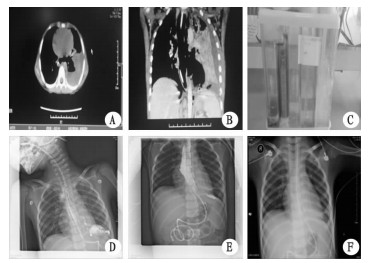

1 资料与方法病例1患儿,男,3岁,因“筷子经口外伤后颈部肿胀3 d,发热气促1 d”于2014年1月收治入院。入院后第2天气促加重,发绀及烦躁不安,高流量面罩吸氧下 (5~6 L/min),氧饱和度 (SO2) 波动予85%~92%转入PICU。入PICU查体:T 40.5 ℃,烦躁不安,感染中毒面容,颈部及上胸部气肿明显,口周发绀,气促,吸气性三凹 (+),两肺呼吸音低,心率160~180次/min,面罩吸氧下氧合83%~88%。予纤维喉镜引导下置入气管插管,发现气管及左右主支气管明显受压。血常规:WBC 30.6×109/L,N82%;CRP 191 mg/L;PCT>10 ng/L。胸部X线片 (图 1A):两肺炎症,左下肺部分不张, 双侧颈部、右腋下皮下积气。颈胸部CT:气管后方颈椎前方 (椎前间隙) 大片气体积聚,右侧液气胸伴右肺不张;纵隔、颈部咽后壁及双侧胸壁皮下积气;两肺炎症,左侧胸腔少许积液 (图 1B)。诊断:颈胸部复合伤伴软组织感染、重症肺炎、脓毒症、呼吸衰竭、右侧脓气胸。

| A、B:入PICU时胸部X线片和颈胸部CT;C:入PICU第20天颈胸部CT;D、E、F:纵隔切开术后12 d颈胸部CT 图 1 第1例患儿影像学演变 |

入PICU后予抗感染,机械通气、右侧胸腔闭式引流等治疗。患儿仍反复高热,呼吸机不能撤离,出现血压下降 (70~75/35~45 mmHg,1 mmHg=0.133 kPa),血乳酸升高 (4~6 mmol/L)。胸腔闭式引流每日引出400~500 mL乳白色液体。胸水常规:黄白色、浑浊,有核细胞9.5×109/L,白细胞分类:多核细胞85%,黏蛋白定性试验 (+),pH 6.8。胸腔积液涂片找到阳性球菌;培养结果为肺炎链球菌。反复多次口服亚甲蓝,引流管中未见蓝染的胸腔积液。胃镜示,食道中断黏膜糜烂,未见明显食道瘘管。入PICU第10天复查胸片示,右侧液气胸好转,两肺渗出增多,纵隔及颈部积气未见吸收,脊柱右侧心影后有半圆形高密度影。入PICU第20天复查颈胸部CT:两肺广泛感染,左侧胸腔积液,局部包裹,咽后及右侧咽旁间隙后纵隔异常囊袋影,伴气体及内容物,考虑纵隔和食道相通 (图 1C)。入PICU第21天胸外科予纵隔脓肿切开引流术,术后予持续鼻胃管胃肠减压、抗感染、制酸、空肠营养管肠内营养支持等治疗。术后第3天体温恢复正常,第4天撤离机械通气,第7天拔除右侧胸腔闭式引流管,第12天复查颈胸部CT:颈部及上纵隔异常囊袋影较前明显缩小,液气胸及两肺感染较前明显好转,拔除空肠管,恢复经口饮食。术后第18天复查CT:颈部及上纵隔异常囊袋影较前吸收,两肺炎症基本吸收,予出院,随访至今健康。

病例2患儿,男,5岁,因“贲门失弛缓症”于2015年9月20日收住消化科行胃镜下球囊扩张治疗。术后第4天发热 (38.5~39.5 ℃)、气促及呼吸困难,查血常规:WBC:19.61×109/L,N 93%,CRP 139 mg/L;胸片示:纵隔积气,左侧胸腔积液,两肺炎症。术后第5天因精神萎靡,呼吸困难进行性加重伴有口周发绀转入PICU。入PICU查体:T39.2 ℃,气促,吸凹 (+),左肺呼吸音低,面罩吸氧下氧合94%~96%。入PICU诊断:球囊扩张术后合并重症肺炎、脓毒症、呼吸衰竭、左侧胸腔积液。予高流量面罩吸氧、胸腔闭式引流、抗感染、制酸治疗。患儿持续高热、呼吸困难进行性加重,入PICU第3天予机械通气;入PICU第4天出现少尿,血肌酐124 μmol/L,予连续床旁血液净化治疗。动态监测炎症指标:WBC 25.6~42.2×109/L,CRP>220 mg/L,PCT>10 ng/L。颈胸部CT示,纵隔积气,左侧液气胸,左肺节段实变不张;食道扩张,食道下端与纵隔及胸腔相通 (见图 2A、B)。胸腔闭式引流出黄绿色浑浊液体 (200~400 mL/d),性状与胃肠引流管一致 (图 2C);胸水常规,黄绿色、浑浊,有核细胞5.5×109/L,白细胞分类:多核细胞80%,pH 4.0~4.8。口服亚甲蓝实验 (+)。食道内镜见食管穿孔位于食管左侧中下段。

| A、B:颈胸部CT箭头所指部位提示食道下端与纵隔及胸腔相通可能;C:黄绿色浑浊胸水,性状与胃内容物一致;D:第一次支架置入术后胃肠钡餐透视 (GI);E:第二次支架置入术后GI;F:二次支架置入术后15 d胸片 图 2 第2例患儿影像学演变 |

入PICU后第6天予置入食道支架 (上杯口直径2.2 cm,长8 cm,管径1.4 cm)、持续胃肠引流、胸腔闭式引流及冲洗、置入空肠营养管、抗感染、制酸、禁食,静脉营养等综合治疗。术后第3天开始恢复小安素牛奶饮食。患儿胸腔闭式引流中出现白色类似于奶汁样液体,200~300 mL/d。复查GI:贲门失弛缓症球囊扩张术后,钡剂部分外溢 (图 2D)。于第一次支架置入术后第7天,胃镜下行支架取出及二次支架重置术 (更换支架上杯口直径2.4 cm,长10 cm,管径1.6 cm)。第二次支架置入术后第2天开始空肠管牛奶滴入,胸腔闭式引流管无液体引流出;术后15 d复查胸片:肺部炎症及胸腔积液基本吸收 (图 2F),术后第20天拔除十二指肠空肠管,术后25 d痊愈出院。随访至今健康。